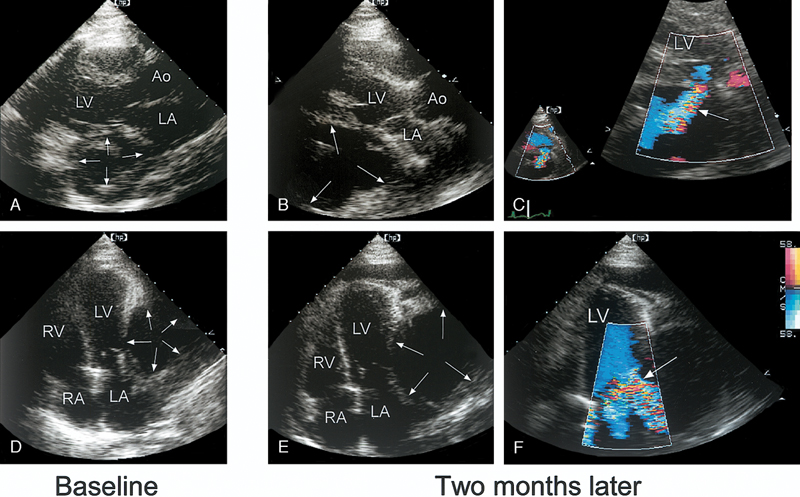

فحوصات تشخيصية لبعض امراض القلب والشرايين التاجية